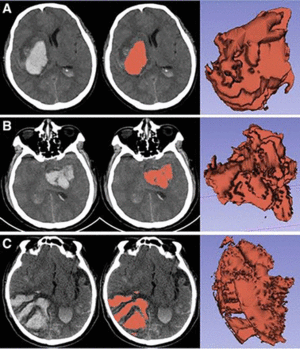

Comparison of the Tada Formula with Software Slicer: Precise and Low-Cost Method for Volume Assessment of Intracerebral Hematoma

Publication: Stroke. 2014 Nov;45(11):3433-5. PMID: 25316277. | PDF Authors: Xu X, Chen X, Zhang J, Zheng Y, Sun G, Yu X, Xu B. Institution: Department of Neurosurgery, People's Liberation Army General Hospital, Beijing, China. Background/Purpose: The Tada (ABC/2) formula has been used widely for volume assessment of intracerebral hematoma. However, the formula is crude for irregularly shaped hematoma. We aimed to compare the accuracy of the ABC/2 formula with open source software 3D Slicer. Methods—Computed tomographic images of 294 patients with spontaneous intracerebral hematoma were collected. Hematoma volumes were assessed with the ABC/2 formula and calculated with software 3D Slicer. Results of these 2 methods were compared with regard to hematoma size and shape. Results—The estimated hematoma volume was 58.41±37.83 cm3 using the ABC/2 formula, compared with 50.38±31.93 cm3 with 3D Slicer (mean percentage deviation, 16.38±9.15%). When allocate patients into groups according to hematoma size, the mean estimation error were 3.24 cm3 (17.72%), 5.85 cm3 (13.72%), and 15.14 cm3 (17.48%) for groups 1, 2, and 3, respectively. When divided by shape, estimation error was 3.33 cm3 (9.76%), 7.19 cm3 (18.37%), and 29.39 cm3 (39.12%) for regular, irregular, and multilobular hematomas. Conclusions—There is significant estimation error using the ABC/2 formula to calculate hematoma volume. Compared with hematoma size, estimation error is more significantly associated with hematoma shape. Funding: